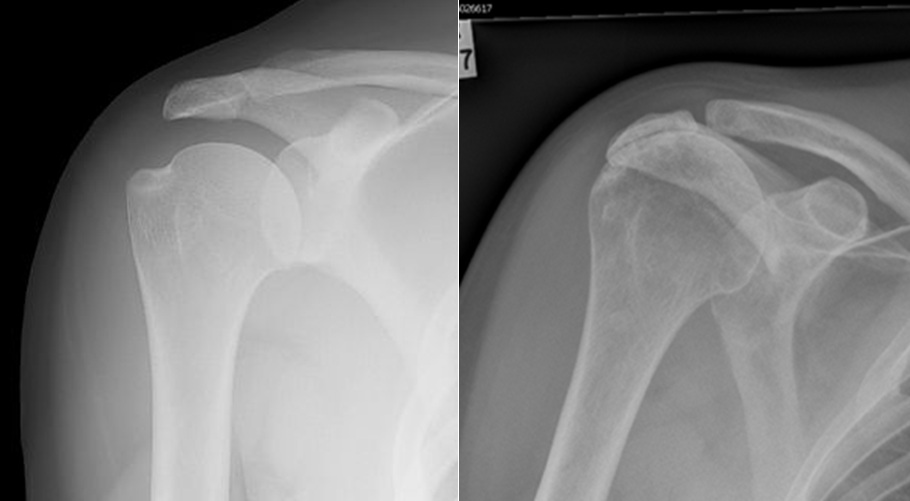

Rotator cuff tear arthropathy. (a) Conventional Xray, (b Rotator Cuff Tear Arthropathy Of Right Shoulder  Identify the risks and physical exam findings associated with a complete rotator cuff tear.   rotator cuff tear arthropathy is a spectrum of degenerative disease that develops due to a rotator cuff deficient shoulder. A rotator cuff tear is an injury to your rotator cuff that can cause shoulder pain and the inability to.   rotator cuff arthropathy is a. Rotator Cuff Tear Arthropathy Of Right Shoulder.